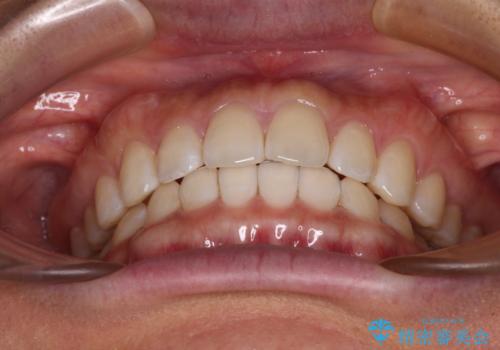

【モニター】前歯のすきっ歯をインビザラインで改善

- 上顎前歯の隙間と口元の突出感を気にして来院された患者様です。

高校生の時に行った矯正治療の後戻りであり、歯列不正は軽度であったので、インビザラインにて治療を行うこととしました。

すきっ歯はあっという間に後戻りを起こすので、可及的に後戻りを防止するために、上下前歯部を舌側からワイヤーで固定しています。

通常は下顎前歯のみに行っていますが、空隙歯列弓では上顎でも行っています。